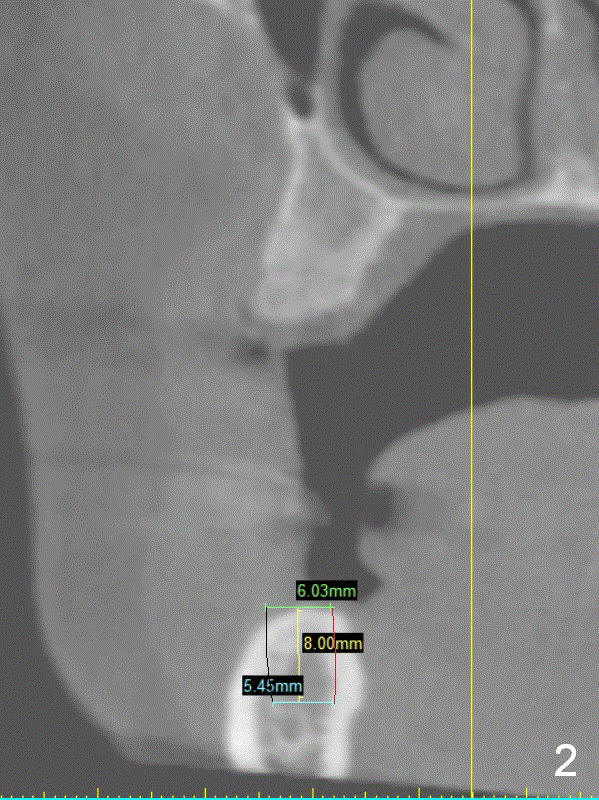

A 49-year-old lady is petit. The crest at #30 is narrow. A small implant is placed. To increase its longevity, the patient should have left 1st molar occlusion. Bone density at #19 is D1 (the cortex), D4 (upper medulla) and D3 (lower medulla) (Fig.1). Bone is wide enough to hold a 6 mm (in diameter) implant, but a 8 mm long implant appears to be too long (Fig.2). Therefore, a 6 or 6.5x6 mm implant appears to be appropriate (Fig.3). How about the bone at #14?